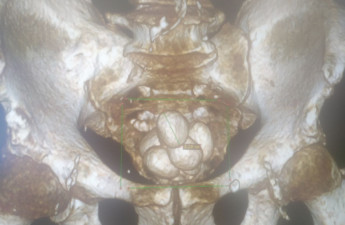

У луцькій лікарні 40-річній пацієнтці видалили шестикілограмову пухлину

За медичною допомогою звернулась 40-річна пацієнтка, яка помітила, що у неї збільшився живіт. Після обстежень виявили та видалили міому великих розмірів.